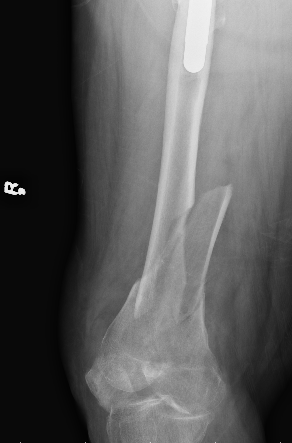

Xray

Options

Lateral plate

Retrograde IM nail